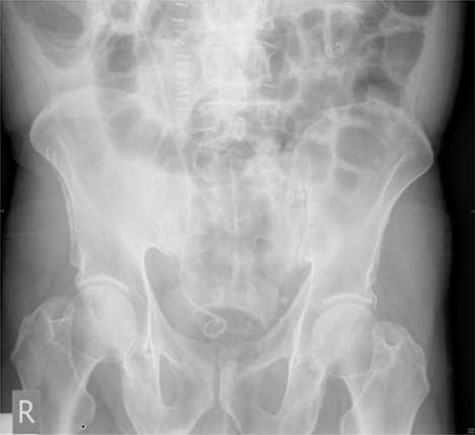

A 72-year-old male with a history of bleeding per rectum underwent an outpatient colonoscopy, which demonstrated a large villous tumour occupying the caecal pole. A staging CT thorax, abdomen and pelvis was subsequently performed confirming the presence of tumour with liver metastases and an incidental 33 × 21 mm calculus in the right renal pelvis with associated hydronephrosis (Fig. 1).

CT scan showing a staghorn calculus in the right renal pelvis with associated hydronephrosis.